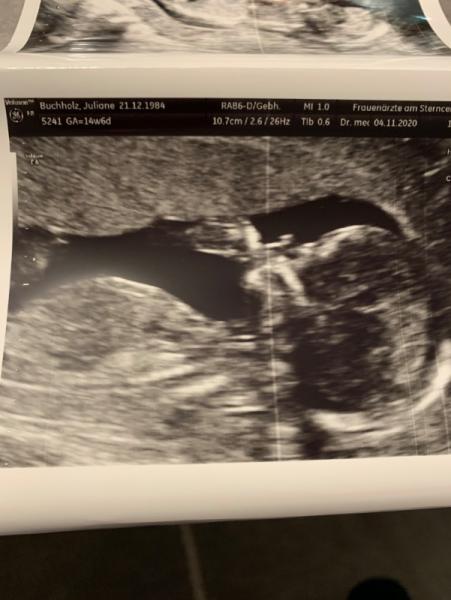

Hallo Mädels, erstmal möchte ich allen gratulieren die heute und gestern einen erfolgreichen Termin beim FA hatten. Es ist schön zu lesen dass bei allen alles gut geht und es auch einige neue Outings gibt. Mein Termin heute war endlich die frühe Feindiagnostik. Da mein Mann ja immer noch im Krankenhaus liegt, kam meine Mutter mit zum Termin. Sie war total erstaunt, was man so alles im Ultraschall sehen und messen kann. Soweit ist bei unserem Sohn alles gut. Er ist etwas kleiner, daher würde sie mich um 5 Tage zurückdatieren von 14+6 auf 14+1. damit kann ich leben, da das bei meinem großen Sohn damals auch war und der im Endeffekt 8 Tage zu früh kam. Dann muss ich ab sofort wieder ASS 150 nehmen, da eine Durchblutung nicht optimal bei mir ist. Das war damals auch schon so. Etwas Sorge hat sie nur wegen dem Bauchumfang vom Baby. Selbst wenn ich heute 14+1 ist der Bauchumfang doch recht klein. Ich soll kurz vor Weihnachten noch mal zur Kontrolle kommen. Dann werden wir weiter sehen. Ich hoffe das normalisiert sich dann wieder. Mein ET ist somit auf den 04.05 gesetzt. Möchte aber trotzdem gerne bei euch bleiben Und das es ein Junge ist, konnte sie heute auch eindeutige erkennen.

Bild zu Heute frühe Feindiagnostik gehabt - Forum für April - Mamis

Hallo und liebe Grüße aus dem Mai Bei uns bist du genauso herzlich Willkommen, ich kann aber verstehen, dass man sich in "seinem" Monat häuslich eingerichtet hat und einfach wohlfühlt! Super schön, dass alles soweit gut aussah und auch die Größe ist bestimmt mit dem nächsten Wachstumsschub wieder völlig passend. Man kann auf dem Foto übrigens deine persönlichen Daten sehen ... Vielleicht lässt du es löschen und lädst es neu ohne Daten hoch?

Danke. Ich schaue bei euch auch immer mal wieder rein. Das mit meinen Daten hab ich total verpeilt jetzt kann ich das Foto aber nicht mehr löschen. Danke für den Hinweis.